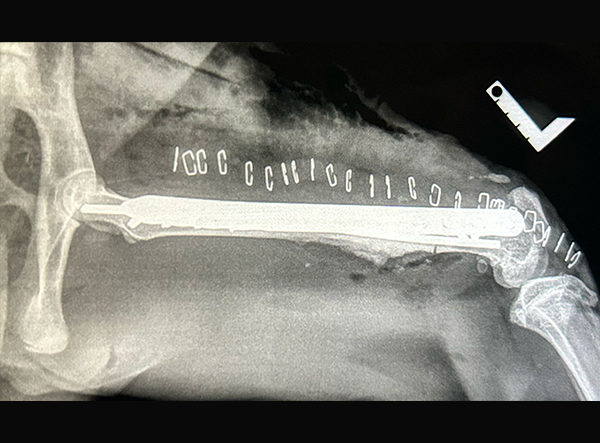

The femur fracture was surgically treated by Dr. Matan Or, using a 3.5 LeiLOX Locking Bridge Plate to provide stable fixation and support the healing process. The LeiLOX system is designed to offer reliable stability while minimizing soft tissue disruption, which is crucial for optimal recovery and a safe return to natural mobility. Its locking mechanism ensures strong fixation, and the bridging technique helps maintain blood supply to the bone, supporting natural bone regeneration.

Implant Used:Â 3.5 LeiLOX Bridge Plate - Stainless Steel

System: LeiLOX Locking System

Manufacturer: Rita Leibinger Medical